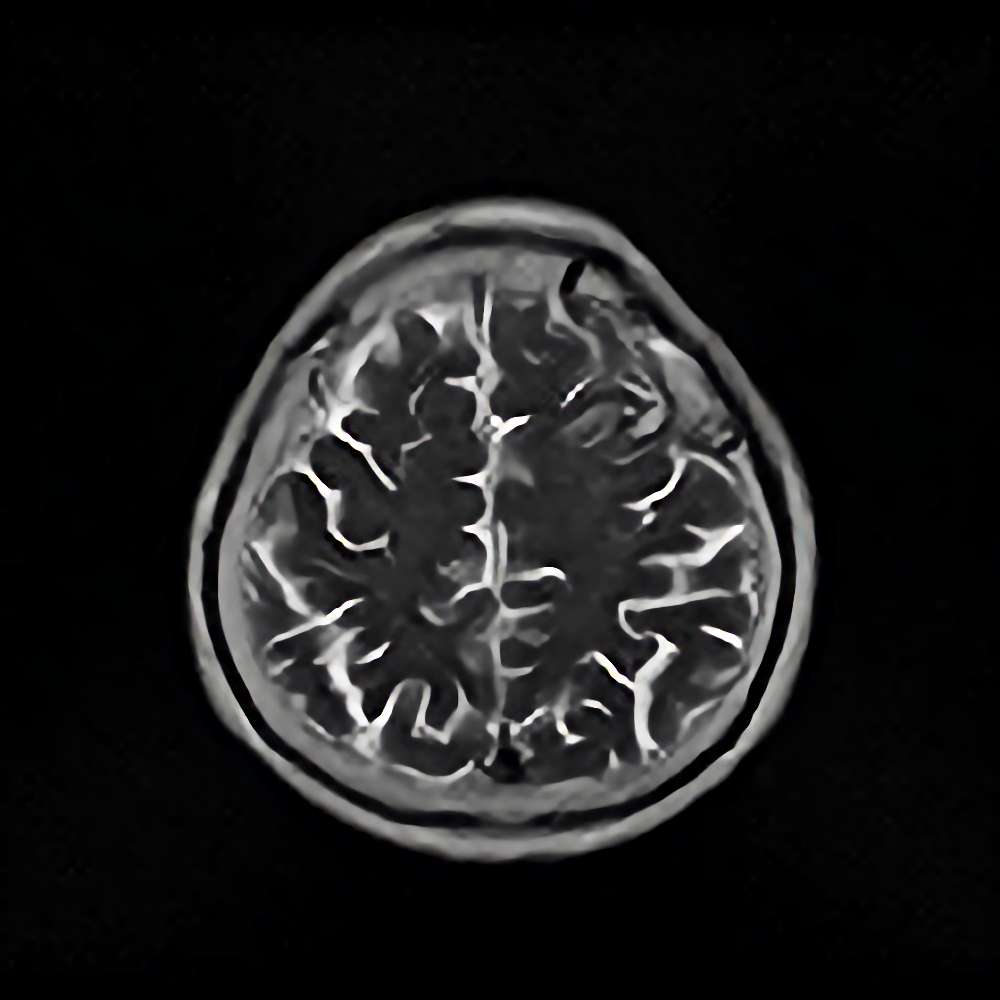

脳腫瘍 手術実績

症例 '16年12月

No.

※ 画像をクリックすると拡大表示します。症例No.は平成29年から起算しています。

年_番号

手術年月

患者年齢

’16_179

'16年12月

70代

病名

術式

備考

脳腫瘍

断層撮影

手術前

1

手術前2

手術後